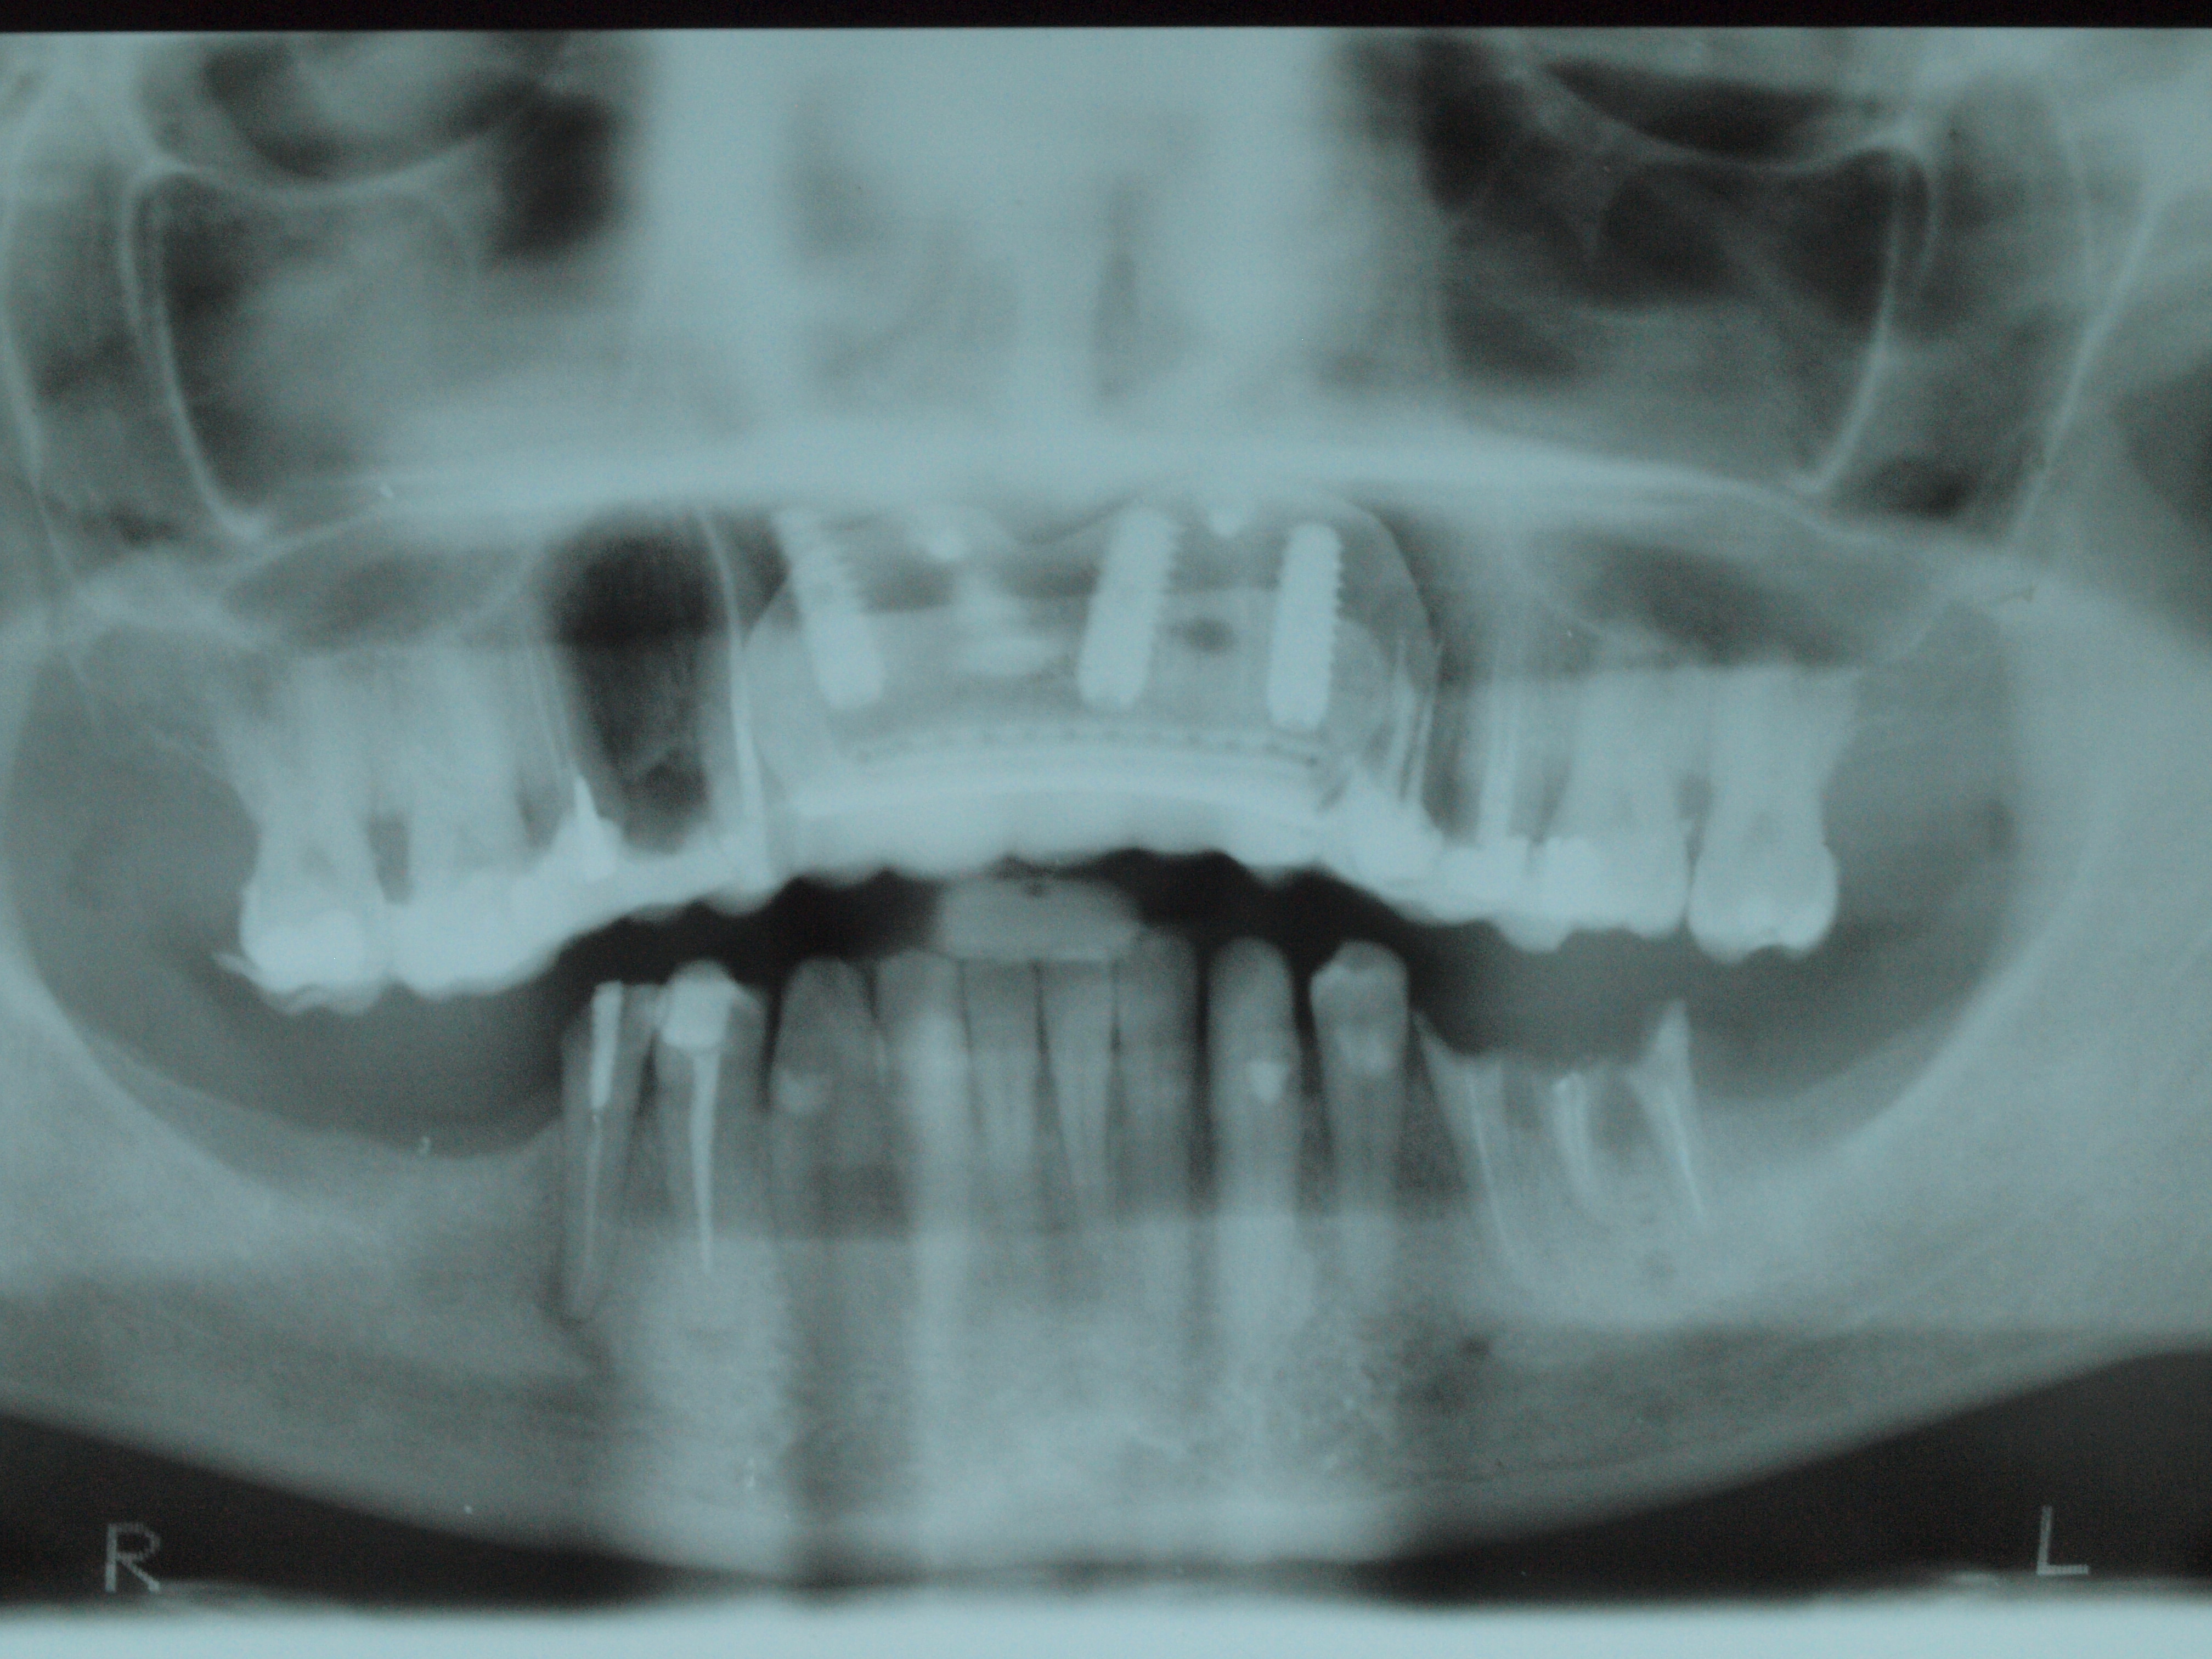

El CBCT confirma una atrofia ósea en zona antero superior así como, pérdida ósea generalizada.

Planificamos exodoncias de restos radiculares, colocación de implantes en zona 1.2, 2.1 y 2.3, junto con una barrera oclusiva de titanio (BO) para regenerar todo el hueso perdido.

Aspecto de la escasez de hueso y la colocación de los implantes dentales.